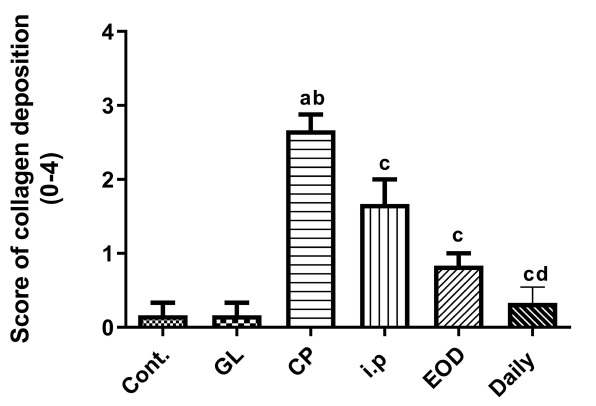

Taken together, these effects not only inhibit inflammation but also reduce collagen deposition and prevent the progression of liver fibrosis (Figure 5).

Data Source/Drug Des Devel Ther. 2020; 14: 2335-2353.

Figure 4 Effects of cisplatin and Ganoderma lucidum on inflammation of liver tissue

Control Group (Cont) |  Ganoderma lucidum Group (GL) |

Cisplatin Group (CP) |  Every Other Day Group (EOD) |

Everyday Group (Daily) |  Intraperitoneal Group (i.p) |

| The arrows point to areas of collagen deposition. | |

Data Source/Drug Des Devel Ther. 2020; 14: 2335-2353.

Figure 5 Effects of cisplatin and Ganoderma lucidum on liver fibrosis